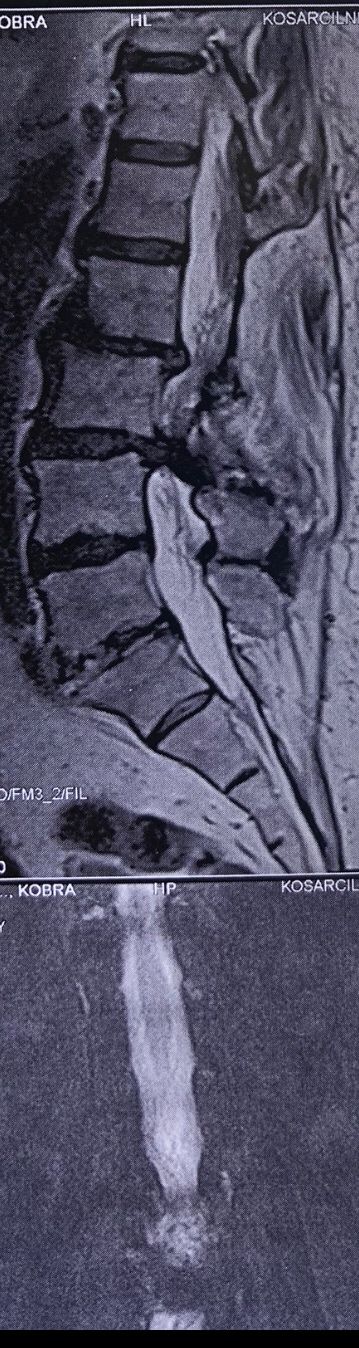

Case 8

Few weeks ago I posted a case with an old TB spondylitis and listhesis with old fractures and severe canal stenosis (in her lower lumbar). A neurosurgeon who works with us at my clinic saw her in the second session

I attached her CT scan. Her PPD which was positive 2 months ago now it’s less than 3 mm. Since this patient has just low back pain and no radicular pain and can walk easily our neurosurgeon suggested no surgery and we emphasized that she has to complete her medication and be under her infectious diseases specialist

And if other signs and symptoms develops have to see surgeon again

Case 9

42 years old female presented to my clinic yesterday on May15/2025 with chronic Low back for 2 yrs. She is from afghanestan and arrived to tehran 3 month ago. Visited pain specialist 3 months ago who just did PPD test and gave her Anti TB medication. In examination just had severe focal khyphosis from L3 to L5 without any tenderness. Her mri was done 2 months ago. Report is in Farsi and mentions of paraspinal puss/ fluid collection esp in psoas muscles, with extension of fluid collection to R pelvic region. Had 2 site of severe canal stenosis due to previous fractures of L3,4,5 and movement of fractured bones to the canal with complete distractions of those levels discs with fusion of L3 to L5

I ordered C T scan of lumbar and pelvic MRI / chest x r and reffered her to neurosurgon and infectious disease specialist to get full assessment and possible hospitalized for biopsy and surgery

As you know doctors of chiropractic would never. give treatment to patients with spinal Discitis/ osteomyelitis/ metastasis/ fracture( absolute chiropractic contraindications for treatment)